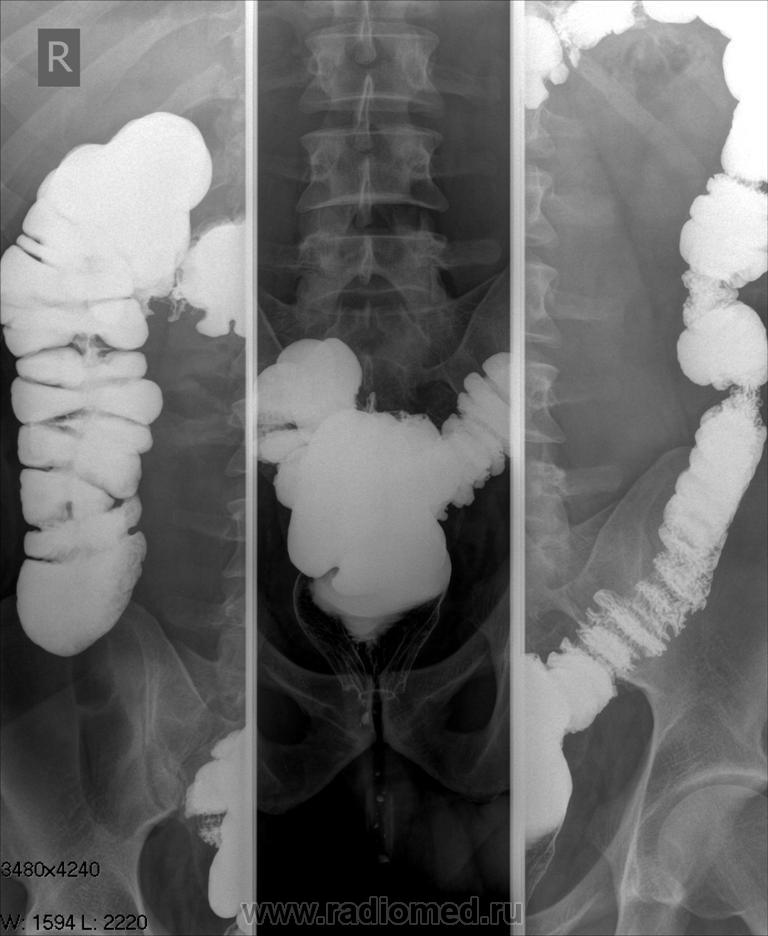

Молодой мужчина, отмечает при дефекации кровь несколько недель. Проводилась ректороманоскопия- выявлены эрозии в прямой кишке, НЯК под вопросом. Ваше мнение по данным ирригоскопии

Выраженный, преимущественно левосторонний колит, явных признаков изъязвлений нет... НЯК пока по рентгеновской карине ставить вероятно рано...

Согласен с Анатолием Владимировичем - банальный, преимущественно левой половины, колит. Рентгенологически НЯКа нет.